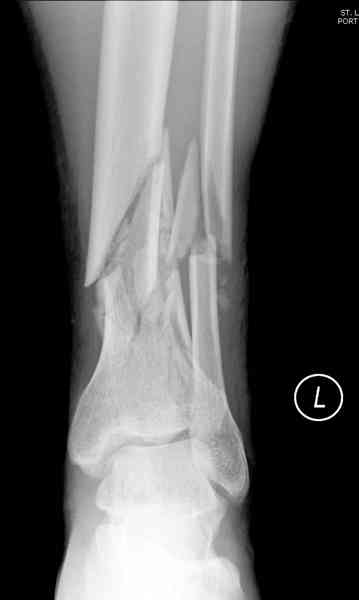

При высокоскоростных переломах редко можно встретить изолированную травму пилона, и в моей практике изолированные травмы большая редкость, поэтому, как дополнение к обсуждаемой теме, решил представить свежий, двухдневной давности случай.

Предыдущей сменой до 4:00 утра по поводу открытого перелома бедра, тибиал плато, пилон и надколенника сделана операция.

Пострадавшему 21 г., травма скоростная, после I&D с расширением раны, на бедре сделана операция ретроградным интрамедуллярным штифтом, остеосинтез с частичной резекцией надколенника и ушивание собственной связки.

На голень наружный фиксатор, рану на бедре ушили (рана была изнутри кнаружи всего 2 см). По протоколу травматических больных, до операции обследован ангиографически, (у больного дистально не смогли определить пульсацию) сосудистый хирург подтвердил проходимость на всем протяжении магистрального сосуда нижней конечности по снимкам ангиограмм.

В настоящее время больной в реанимации по поводу Черепно Мозговой Травмы и состояние улучшается. Запланировал ушивание раны в пятницу, если позволит состояние мягких тканей и при отсутстви отека возможно удастся просунуть перкутанномедиальную пластину.

КТ пилона имеем.